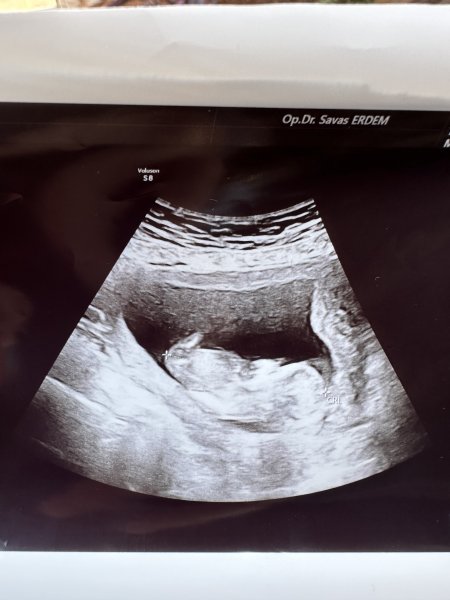

Hayatım resim tam görünmüyor da ne istiyorsun sen bu resim sonucuna göre cinsiyet tahmini mi istiyorsun ?

Hayatım elinde başka resim var mı NUB a göre cinsiyet tahmini yapmak isterim ama bu resim malesef yetersiz baya parlamış görünmüyor apış bölümü :D:D

Selamlar bi tanem vallahi tam olarak hatta hiç bişi göremiyorum daha daha doğrusu, ilgili resimdeki veri, cinsiyet tahmini için yeterli değil. Bak hemen aşağıdaki nub teorisine göre bebek cinsiyet tahmini yapmak istiyorum ama o alan yok aşağıdaki konuyu incele bitanem.